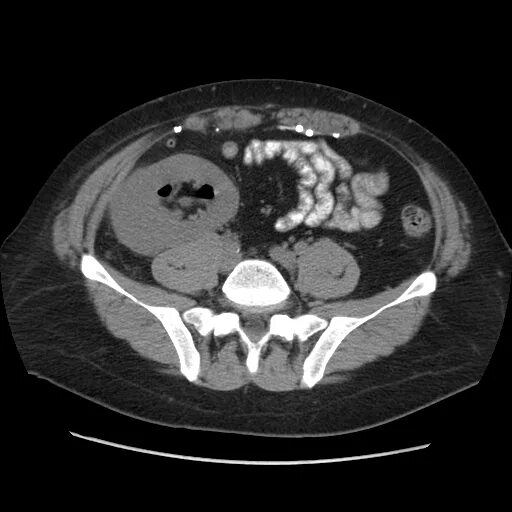

Пиелонефрит кт